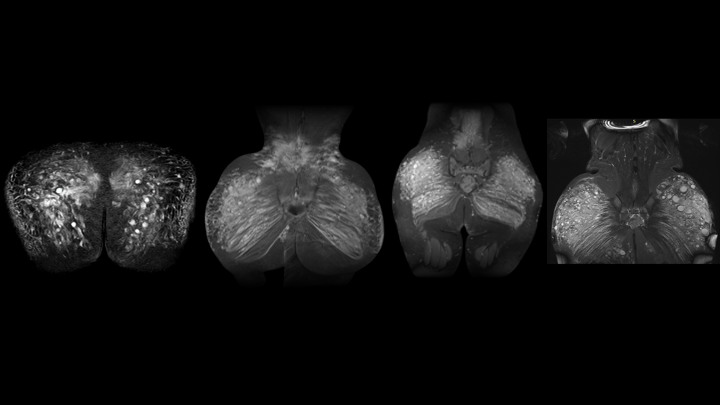

La resonancia magnética (RMN) es fundamental en el proceso de extracción de biopolímeros, porque permite identificar con exactitud la localización, volumen y nivel de infiltración de los biopolímeros en los tejidos.

A diferencia de otros estudios de imagen como la ecografía o la tomografía computarizada, la resonancia magnética es el único método que proporciona una visualización detallada de los biopolímeros y su impacto en los tejidos circundantes.

• Permite localizar con precisión los biopolímeros y su distribución en el tejido.

• Determina el grado de migración del material hacia áreas como la parte baja de la espalda, muslos o región lumbar.

• Ayuda a identificar procesos inflamatorios crónicos, fibrosis o necrosis en la zona afectada.

• Generalmente se enfoca en la región glútea y zonas circundantes donde pueda haber migración del material.

Una vez obtenidos los resultados de la resonancia magnética, el cirujano puede determinar:

• El mejor abordaje quirúrgico, seleccionando entre técnicas como la extracción en bloque, tres colgajos, alas de gaviota o técnica vertical.

• La extensión de la cirugía, ajustando el plan según la cantidad y ubicación del material infiltrado.

• La estrategia de reconstrucción glútea, dependiendo del daño en los tejidos circundantes.

La Resonancia Magnética es una herramienta fundamental en la extracción de biopolímeros, ya que proporciona información detallada sobre la ubicación y el estado de estas sustancias modelantes en el cuerpo.

Su uso permite una planificación quirúrgica precisa, reduce el riesgo de complicaciones y mejora los resultados postoperatorios. En este tipo de cirugías, optar por una resonancia de 3 Teslas es clave para garantizar un diagnóstico exacto y una intervención segura y efectiva.